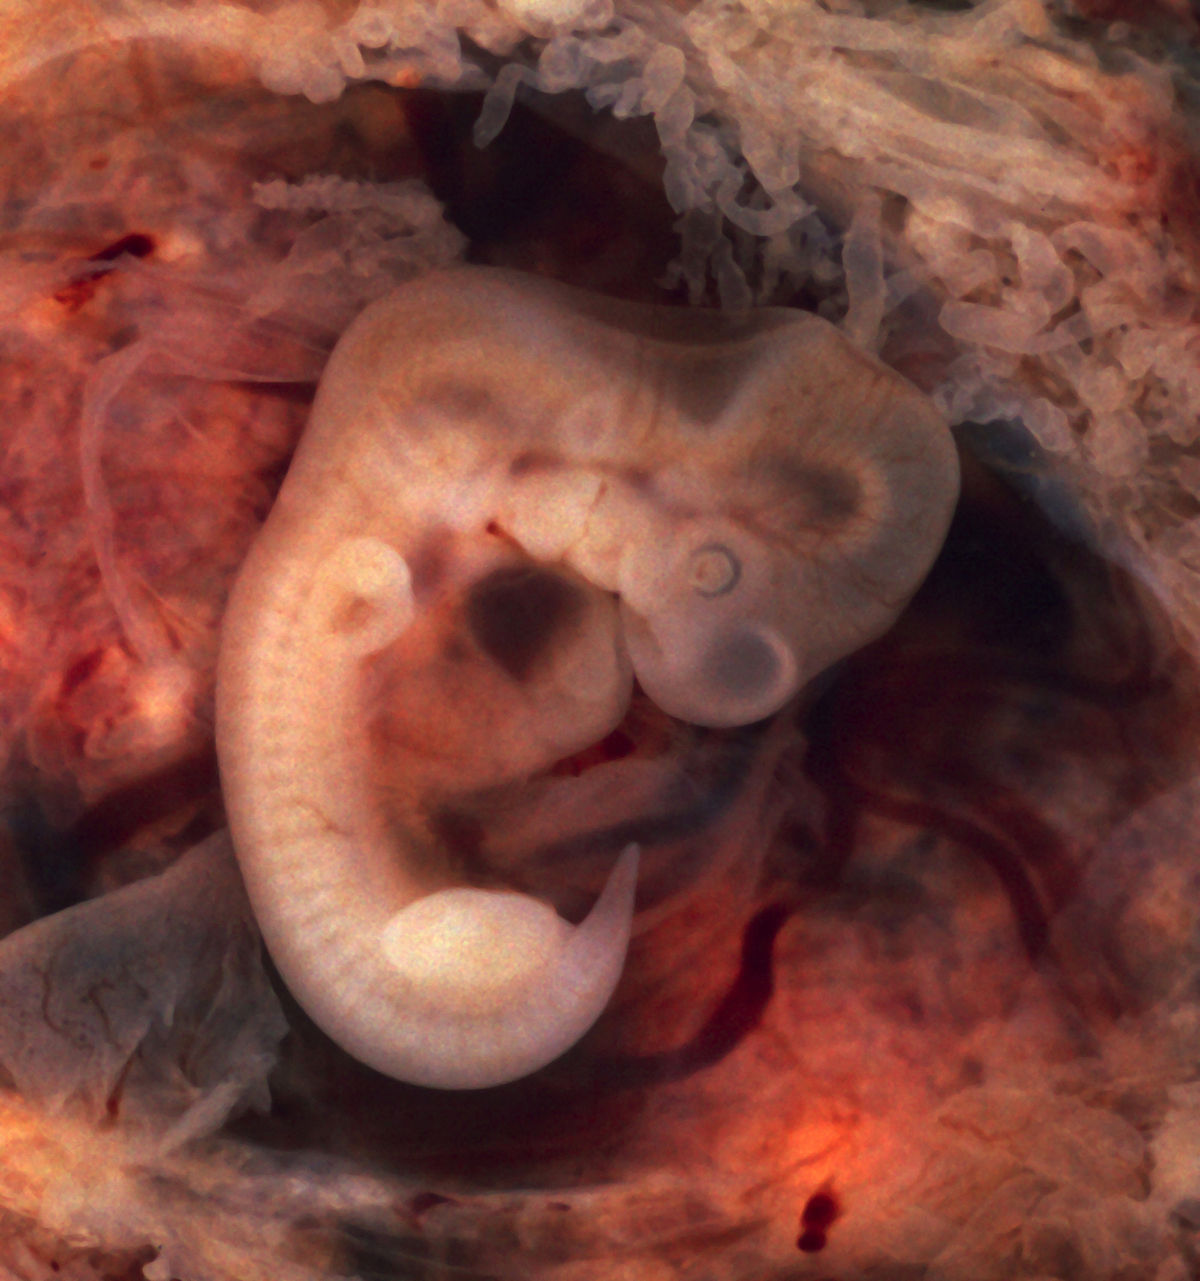

Этапы развития эмбриона человека: 14 недель